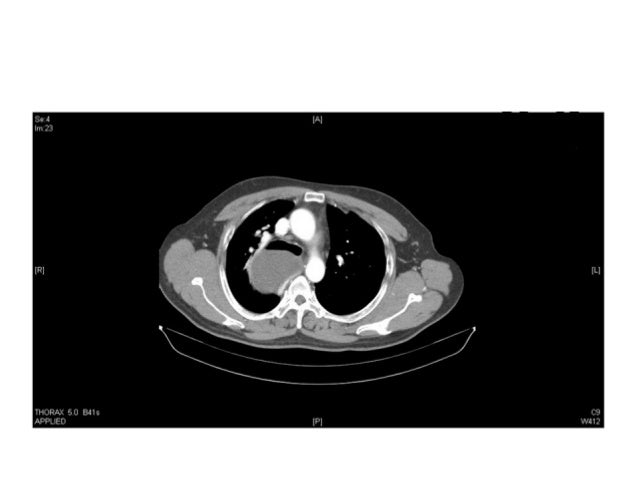

To underline a schematic approach to differentiate mediastinal masses.

It is helpful to identify the location of the mass since this significantly reduces the breadth of the differential diagnosis. 33% of all masses present in patients less than 15 years old if small, usually asymptomatic and found incidentally (cautious work up) if large, usually present with respiratory distress (frantic work up). However, it may occasionally present as an appreciable anterior mediastinal mass.